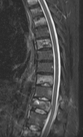

Eski Lomber Stabilizasyon Sistemi Altında Kırık (2)

Ağustos 2023